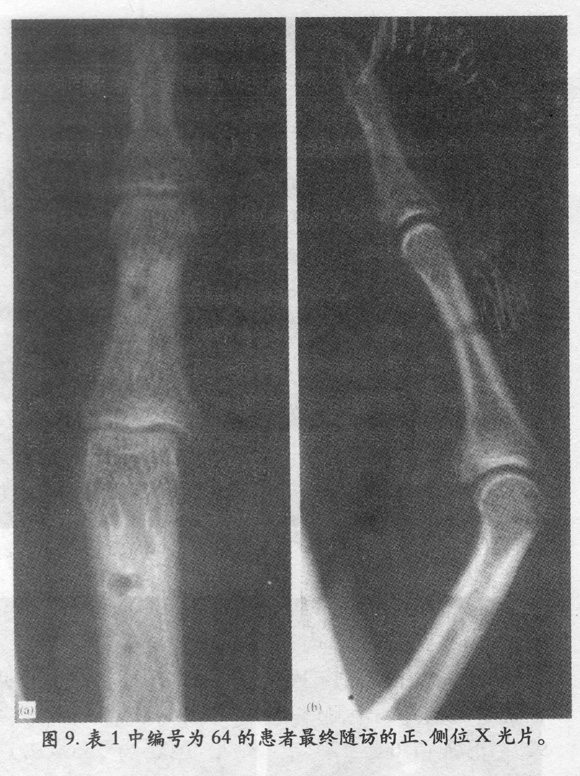

应用S-QUATTRO治疗急性指骨关节内骨折